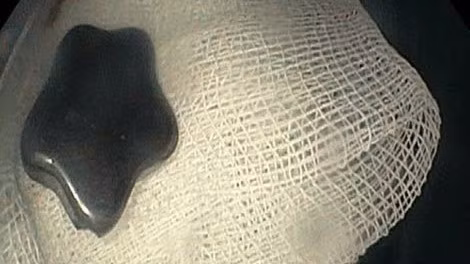

Bệnh nhi N.N.N.Y (ngụ TP Thủ Đức) nhập viện trong tình trạng mắc nghẹn, đau vùng cổ, khó thở nhẹ. Kết quả chụp X-quang ghi nhận, dị vật hình ngôi sao cản quang mắc tại vùng cổ.

Đối với trường hợp bệnh nhi Y., vị trí mắc tại thực quản trên, bề mặt trơn láng. Các bác sĩ tiến hành dùng kềm cá sấu gắp dị vật nhưng thủ thuật thất bại.

Do đó, các bác sĩ thực hiện phương án theo nhu động thực quản đẩy dị vật xuống lòng dạ dày, tiến hành dùng vợt lấy dị vật.